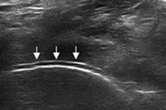

“双轨征”

跖趾关节软骨表面可见高回声不规则增强的软骨滑膜边缘线,呈“双轨征”。

软骨表面回声增强,与深面的骨性关节面强回声线形成“双轨征”。